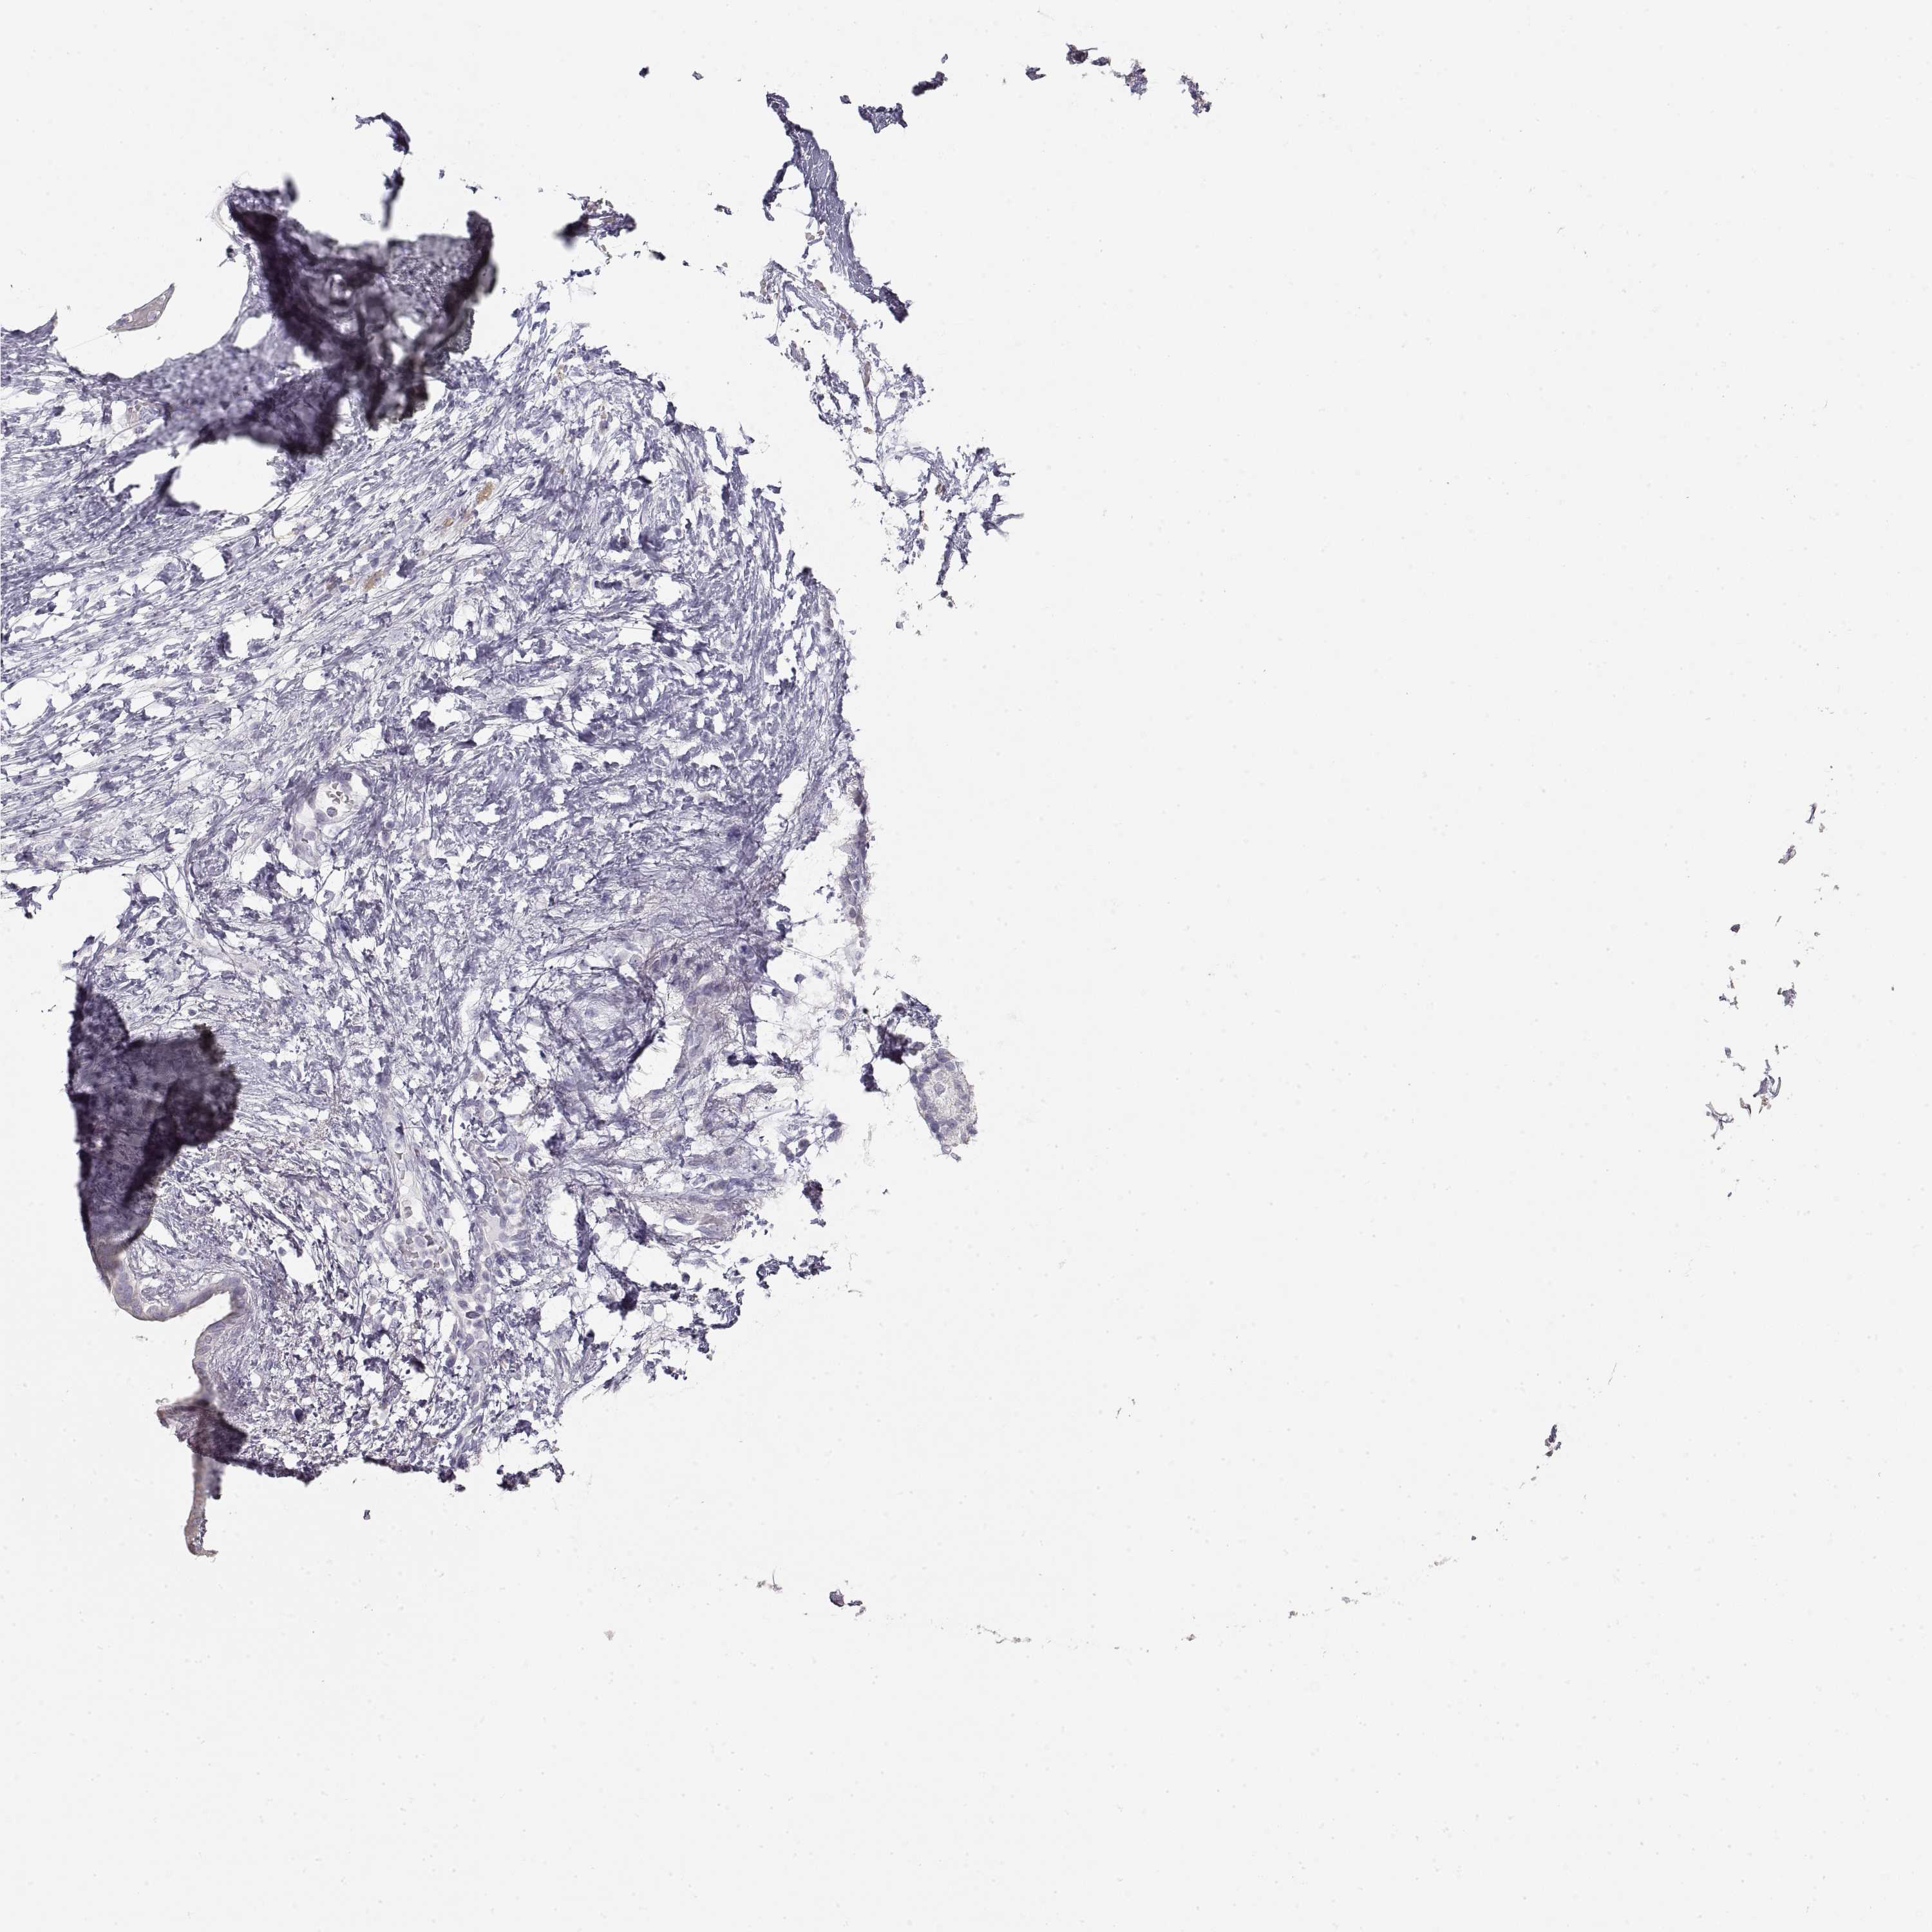

PANCREATIC CANCER - Protein expressioni

A mouse-over function shows sample information and annotation data. Click on an image to view it in a full screen mode. Samples can be filtered based on level of antibody staining by selecting one or several of the following categories: high, medium, low and not detected. The assay and annotation is described here.

Note that samples used for immunohistochemistry by the Human Protein Atlas do not correspond to samples in the TCGA dataset.

Antibody stainingi

Antibody staining in the annotated cell types in the current human tissue is reported as not detected, low, medium, or high, based on conventional immunohistochemistry profiling in selected tissues. This score is based on the combination of the staining intensity and fraction of stained cells.

Each image is clickable and will lead to virtual microscopy that enables deeper exploration of all samples and also displays staining intensity scores, fraction scores and subcellular localization as well as patient and tissue information for each sample.

Antibody HPA054061

Antibody HPA071198

Staining

High

Medium

Low

Not detected

Intensity

Strong

Moderate

Weak

Negative

Quantity

>75%

75%-25%

<25%

None

Location

Nuclear

Cytoplasmic/membranous

Cytoplasmic/membranous,nuclear

Adenocarcinoma, NOS